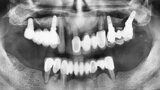

Kombinace standardních a ultrakrátkých implantátů při rehabilitaci celých úst